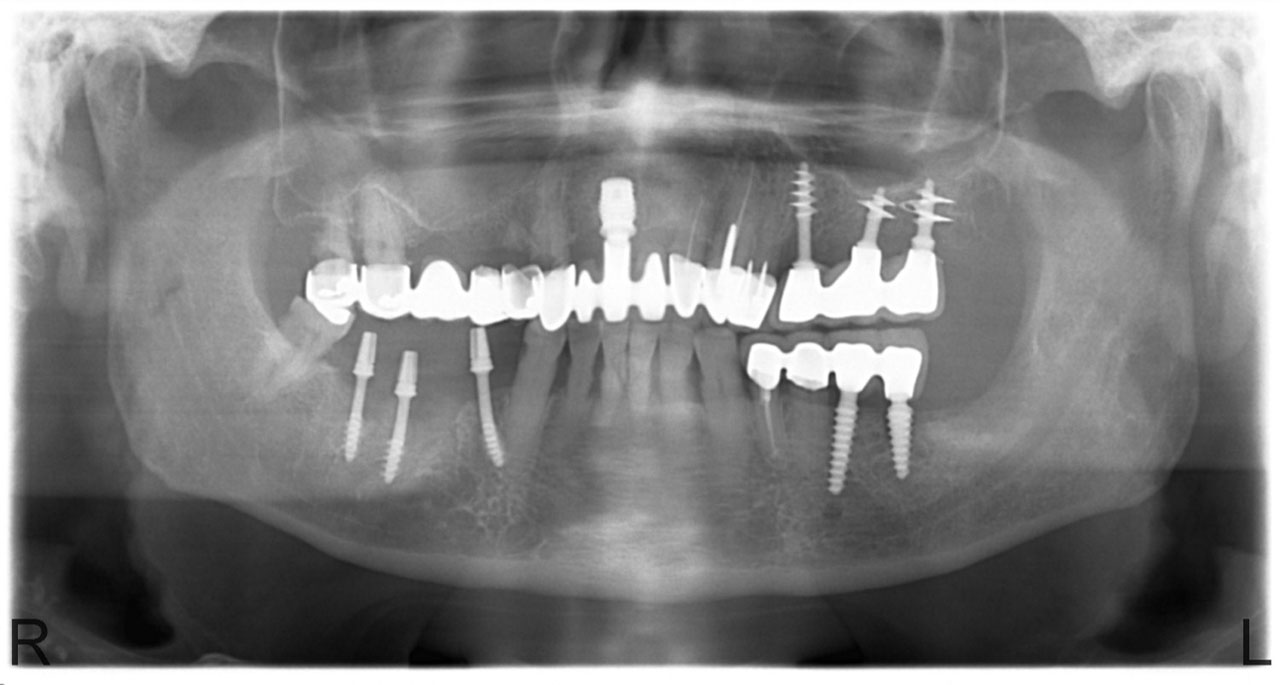

• esettanulmany-03

Imlantáció után,bal oldalon már a végleges hidakkal, jobb oldalon még csak az implantátumok.